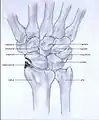

Stages

Post-traumatic osteoarthritis can be classified into four stages.[1][6] These stages are similar between SLAC and SNAC wrists. Each stage has a different treatment.

- Stage I: the osteoarthritis is only localized in the distal scaphoid and radial styloid.

- Stage II: the osteoarthritis is localized in the entire radioscaphoid joint.

- Stage III: the osteoarthritis is localized in the entire radioscaphoid joint with involvement of the capitolunate joint.

- Stage IV: the osteoarthritis is located in the entire radiocarpal joint and in the intercarpal joints. It also may involve the distal radio-ulnar joint (DRUJ).

Stage I

Stage II